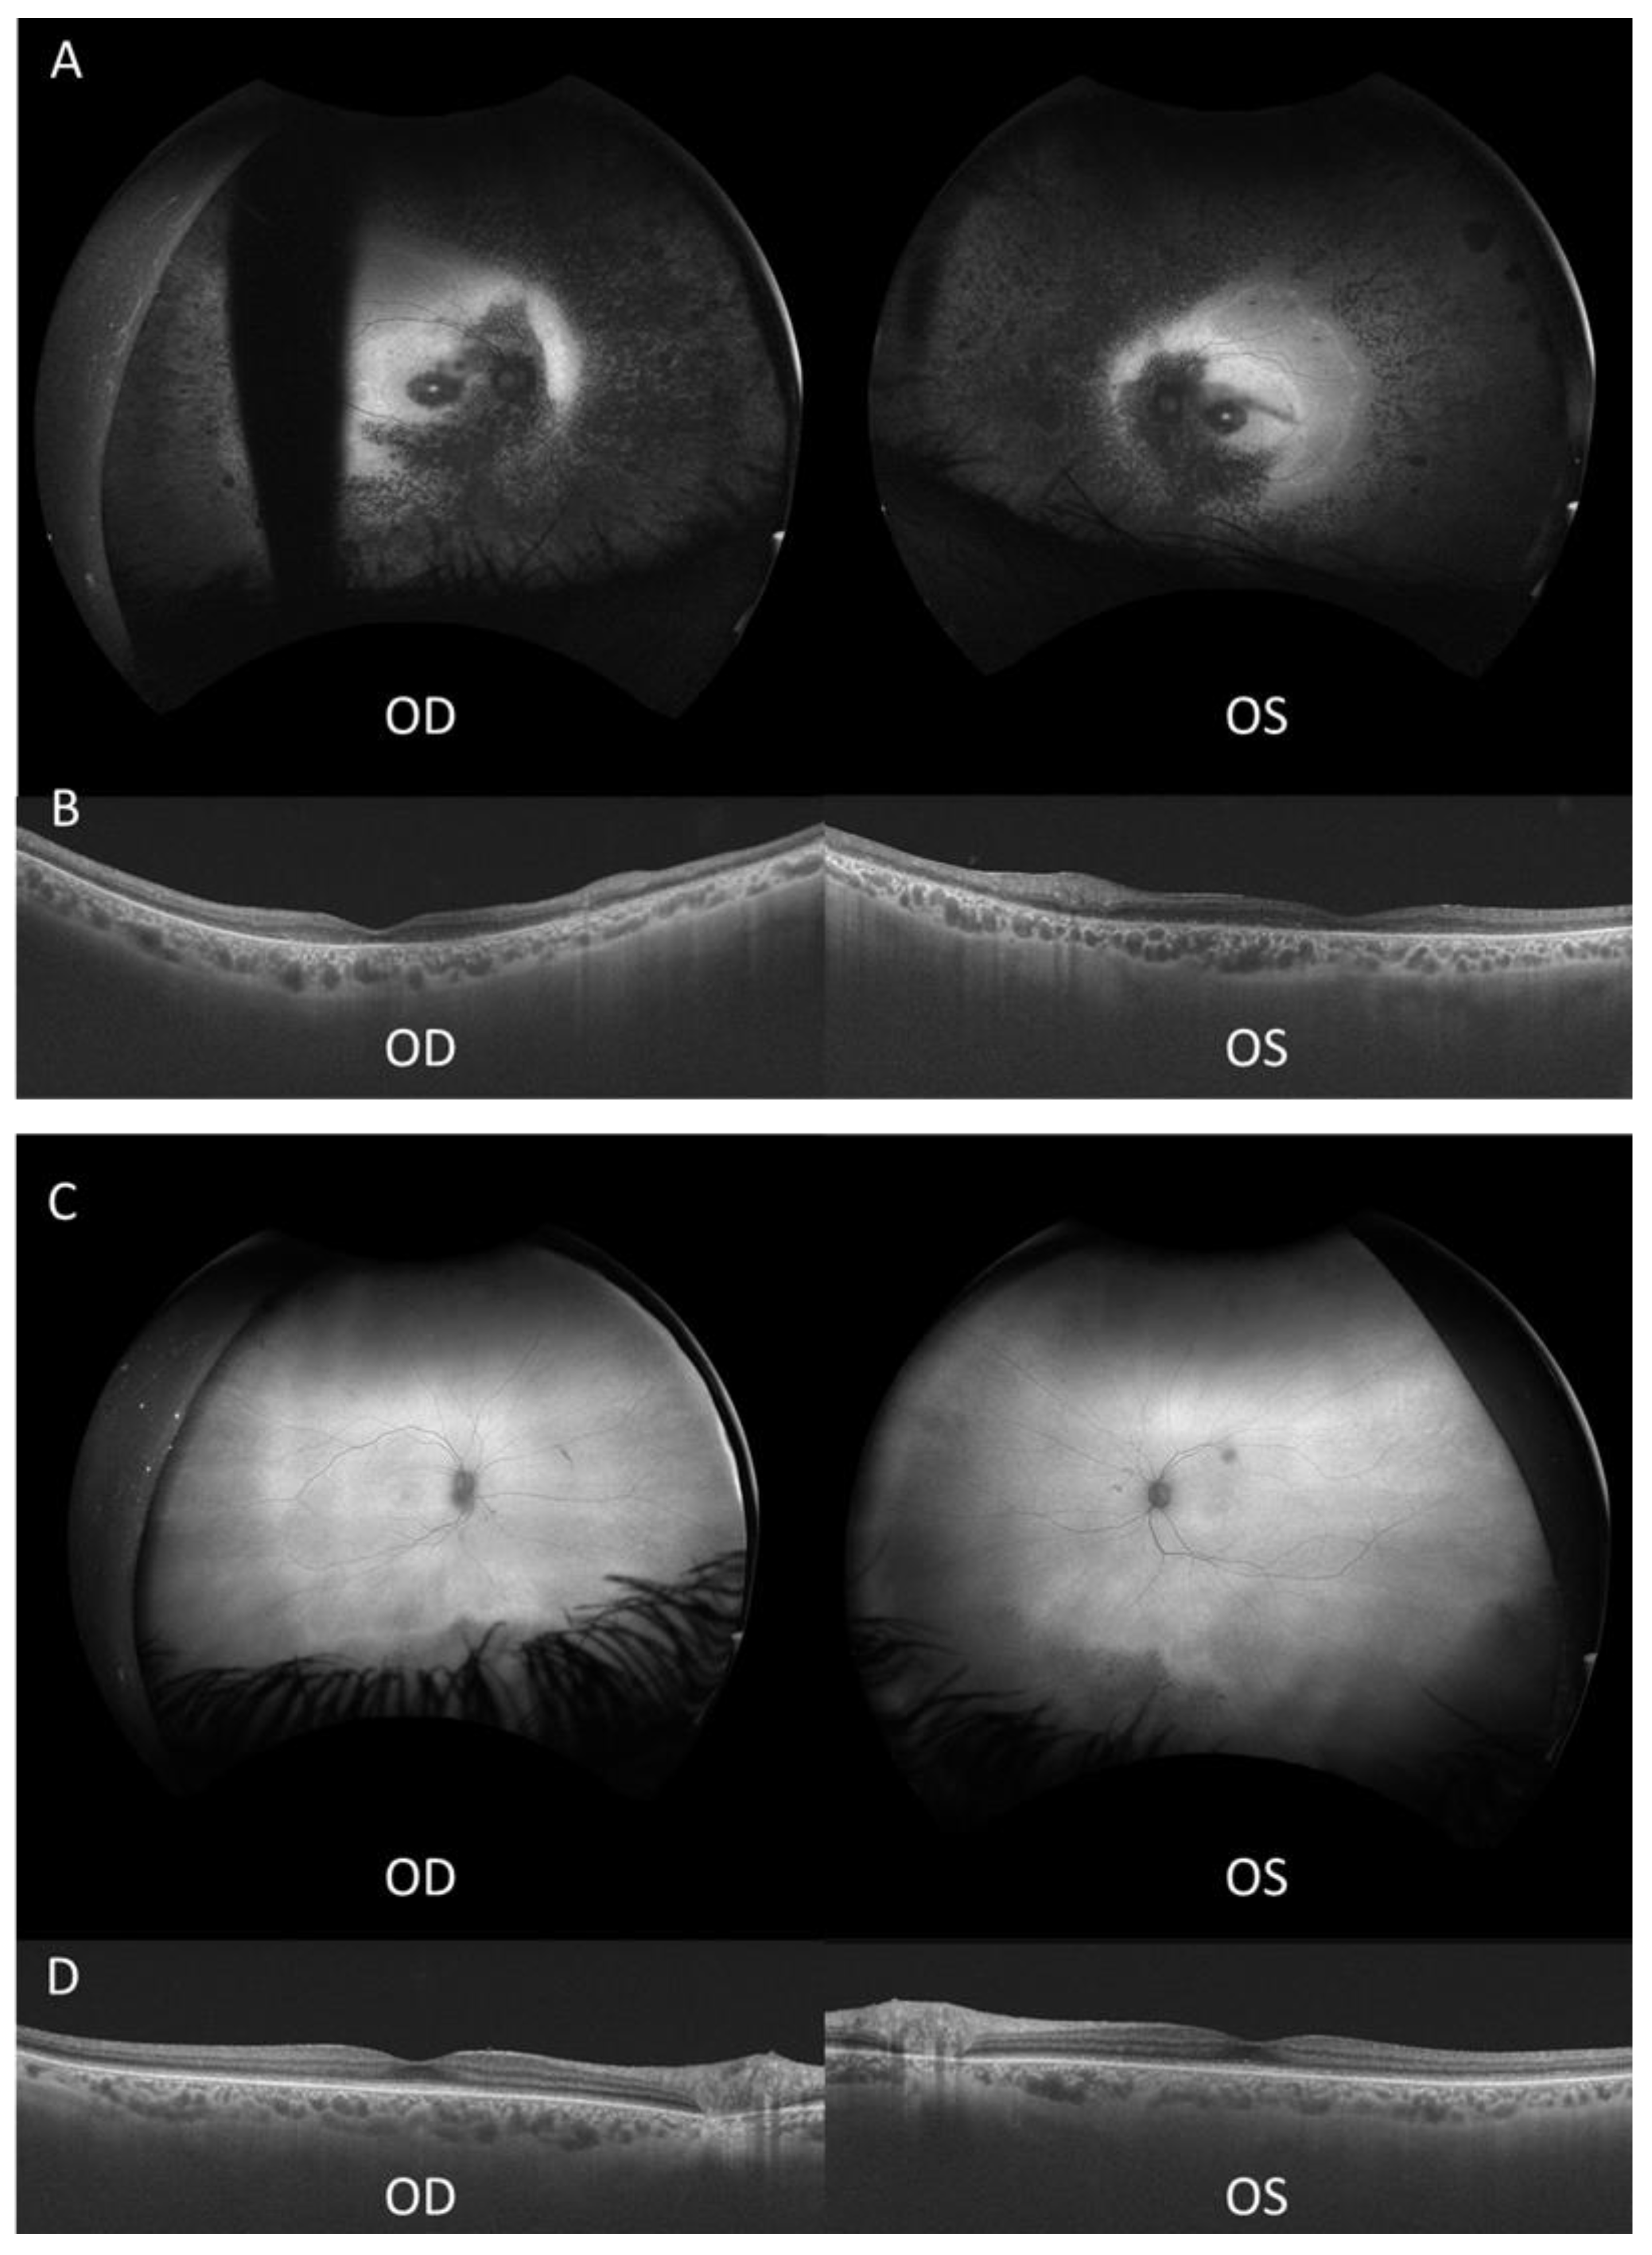

Proband 1 (II-2, Figure 1) is a 51-year-old male diagnosed with retinitis pigmentosa (RP) at age 3, initially presenting with photophobia. Recent symptoms include worsening of night blindness and difficulty adjusting to varying light conditions. At the time of referral (age 50), the ophthalmic examination revealed severe central visual impairment (20/500 OD, 20/640 OS) and peripheral visual field defects. Anterior segment examination showed central subcapsular cataract in both eyes, with intraocular pressure (IOP) of 20 mmHg bilaterally. Fundus examination showed optic disc pallor, 360° pigmentary changes and bone spicules, macular atrophy, and thinned retinal vessels. FAF revealed extensive hypoautofluorescence in the peripheral retina, extending into the superior and inferior nasal quadrants, with a narrow hyperautofluorescent ring around the fovea (Figure 2A). The OCT confirmed the loss of the outer retinal layers and retinal pigment epithelium (RPE), consistent with macular atrophy (Figure 2B). Based on these findings, a clinical diagnosis of early onset cone-rod dystrophy was made.

Proband 2 (II-1, Figure 1), the 53-year-old sister of proband 1, was referred to our clinic at age 51 after a consultation in ophthalmology at a private clinic due to complaints of eye fatigue. She presented milder symptoms, including mild photophobia and peripheral visual field loss, especially in the lower and right lateral areas, but denied experiencing nyctalopia. Upon further inquiry, she recalled childhood difficulties in tracking objects and interpreting visual cues, though she attributed these issues to clumsiness at the time. At presentation, the ophthalmic examination showed moderate visual impairment (20/100 OD, 20/50 OS) with posterior subcapsular cataracts. Fundus examination revealed pigmentary changes and bone spicules in the inferior and temporal peripheral retina of both eyes, although less pronounced than in her brother. Retinal vasculature and optic disc were within normal limits. FAF demonstrated localized hypoautofluorescent patches in the inferior and temporal peripheral retina of both eyes, sparing the posterior pole, with a hyperautofluorescent demarcation line (Figure 2C). The OCT showed minimal structural abnormalities, with slight fusion and blurring of the outer retinal layers at the subfoveal level, but preservation of the inner retina and a well-defined foveal contour (Figure 2D). ffERG showed preserved scotopic responses with delayed and reduced photopic cone responses, and abolition of the flicker response. MfERG revealed markedly reduced central amplitudes (Supplementary Figure S1). These findings suggest a milder form of cone-rod dystrophy.

Figure 2. Ultra-widefield autofluorescence (FAF) and optical coherence tomography (OCT) of both eyes in each sibling. (A) FAF image of proband 1, with a blinking artifact in the OD. (B) OCT of proband 1. (C) FAF image of proband 2. (D) OCT of proband 2 showing discontinuities in the external retinal layers. OD, right eye; OS, left eye.